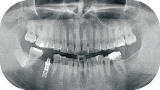

表面からは見つけ難い

むし歯や神経の状態も把握

前歯から奥歯まで一度に撮影できるため、肉眼では確認できない口腔内の全体像を把握できます。視診や口腔内写真だけでは分かりにくいむし歯の有無や親知らず、歯周病の状態を確認することができます。